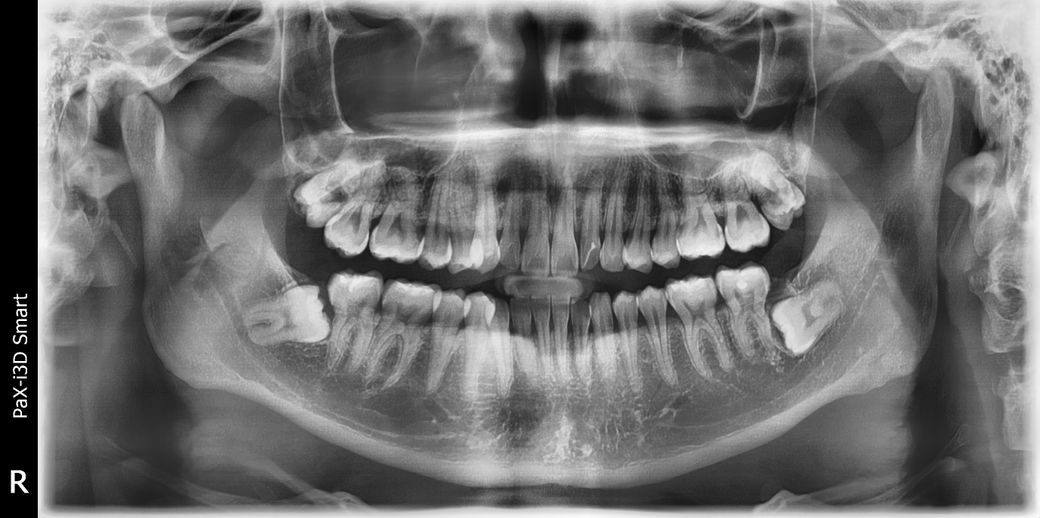

치과 어금니 엑스레이 좀 봐주세요!!!!

치과 어금니 좀 봐주세요. 어금니 안쪽이 썩었다고 하는데 뒷면을 봐도 육안으로 확인이 안되요. 앞니쪽은 뒷면이 보이는데 어금니는 도통 안 보이네요.

치근단 방사선 사진 찍어보면 더 정확히 알 수 있을 것 같은데 충치 의심되는 쪽은 왼쪽 위 첫번째 어금니, 오른쪽 아래 첫번째 어금니입니다 (엑스레이 사진상에서는 좌우 반전입니다)

방사선 사진으로는 좌측 위에 어금니 인접면에 충치가 보이고 있습니다 하지만 정확한 확인하기 위해서는 육안으로 화분이 필요할 것으로 생각됩니다.

큰어금니 사이에 충치가 잇어 보입니다. 인레이 또는 크라운 치료를 하셔야될수도 잇을것같습니다.

파노라마 사진은 전체적인 판독을 위한 것이니 각 치아에 대한 진단이 궁금하시면 치근단 사진 부탁드립니다.

해당 x-ray 사진으로는 개별적인 치아의 상태 파악에 어려움이 있습니다. 전체적으로 조명하는데는 중요한 사진이지만 치아 하나하나를 개별적으로 판단하기 위해서는 치아마다 사진을 찍어봐야 합니다. 현재 사진에는 중첩되는 부분도 많으므로 pa 사진 등이 필요합니다.